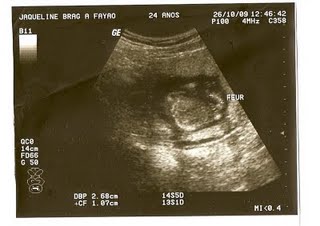

Ultra morfológica

Finalmente chegou o dia da morfológica. Fiz dia 16/12/2009 e fiquei muito feliz por ver o Bryan se mexendo muito, e comecei a sentir cada vez mais os seus chutes, que ele sempre dá pela madrugada...

Vou postar as fotinhas da ultra, meu príncipe está se desenvolvendo muito rápido, uma cmparação é que ele cresceu mais de 1cm por dia...Desse jeito ele vai nascer enorme...kkkk

Laudo ultra:

Feto único, em situação longitudinal, apresentação cefálica com dorso à direita, movimentando-se ativamente.

BCF com frequência e ritmo normais.

DBP: 51mm Circunferência cefálica: 185mm DCT:23mm

Comprimento femoral: 38mm Comprimento umeral: 37mm

Circunferência abdominal: 152mm

Comprimento ulna: 28mm. Comprimento tíbia: 33mm

Peso aproximado: 410gr

Estatura fetal estimada: 26cm

Biometria fetal compatível com evolução em torno de 21 semanas

Placenta anterior de espessura normal, normoimplantada, grau 0 de maturação.

Cordão umbilical formado por três vasos, normoimplantado.

Índice de líquido amniótico normal.

Crânio e encéfalo de aspecto normal.

Não foram observadas alterações o fechamento do tubo neural.

Face anatômica sem sinais de assimetria ou lábio leporino.

Osso nasal de dimensões normais medindo 7mm

Situs solitus. Coração formado por 04 câmaras.

Fígado e pulmões homogêneos.

Ausência de derrame pleural, pericárdio ou ascite.

Rins tópicos, de volume normal sem evidências de hidronefrose ou cistos.

Membros individualizados sem alterações, exibindo movimentos ativos.

Bexiga e estômago contendo líquido.

Genitália externa masculina.

Colo uterino bem configurado.

Doppler umbilical normal.